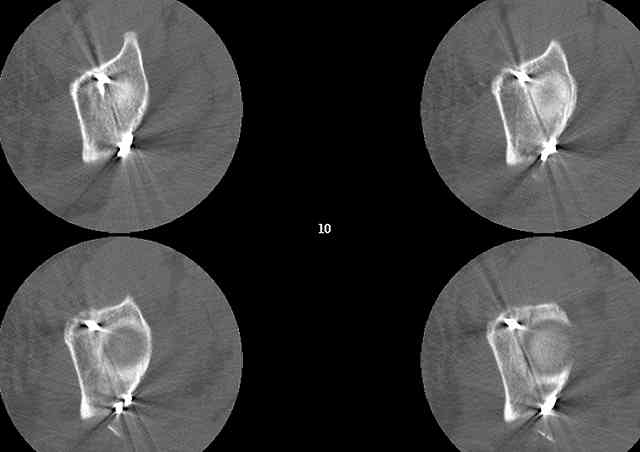

OK, now we're inserting the drill percutaneosuy using a sleeve. This fluoro shot is not for this patient (notice no clamp) but I was too lazy to go searching the PACS for one with the clamp on, so pretend...I'll save the next ones and send along...the imaging is the same and the clamp doesn't obstruct imaging other than very rarely...you can always tilt the C-arm a bit to clear it if the clamp obstructs the exact spot that you'd like to see. We'll assume that everyone knows the safe zone for a medullary ramus screw. Use a calibrated drill and sleeve of known length to simplify your life...or use Alex's fancy cannulated screws...I like 3.5mm screws because the oscillating 2.5mm drill bounces and remains intraosseus when it oscillates and contacts endosteal cortical ramus... so will the screw, and like a long bent screw IF the fracture is clamped... if unclamped, when the screw contacts the endosteum, it pushes the reduction apart instead of bouncing. The big 7mm cannulated screws fit few patients and extrude...we very rarely use them any more...you'll see an old one later.

Prone Obturator-Outlet

Screw insertion using the obturator-outlet combination image.

12.Prone Obturator-Outlet

Same with a contoured pelvic reconstruction plate applied and tensioned.

Prone Iliac Oblique

The other oblique reveals the extra-articular implants.... you know the AC screw is extra-articular from the other views.

Routine Fixation

AC Screw

PC Neutr Plate

Others

The unstable caudal segment is secured by the lower 2 plate screws and the AC medullary screw... always assure that your fixation is sufficient to defeat the instability... part of your prop plan... but assure it before you close... it¹s your last chance... you shouldn't have to be pushing on the hip in contorted ways to determine your fixation stability...you can if that makes you 'comfortable'.